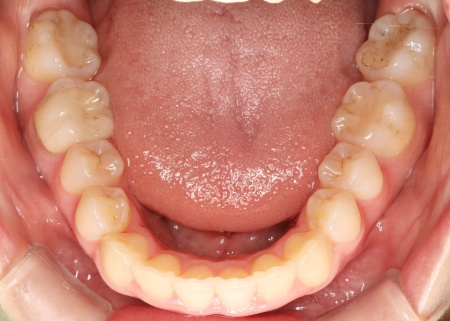

拝見したところ、上下の歯が正しく並ぶためのスペースが足りず、デコボコに生えていました。

とくに、犬歯が正しい歯並びから大きく飛び出した位置に生えており、いわゆる八重歯の状態です。

また、奥歯を噛み合わせた際に上下前歯が噛み合わず隙間ができる開咬(かいこう)も認められました。